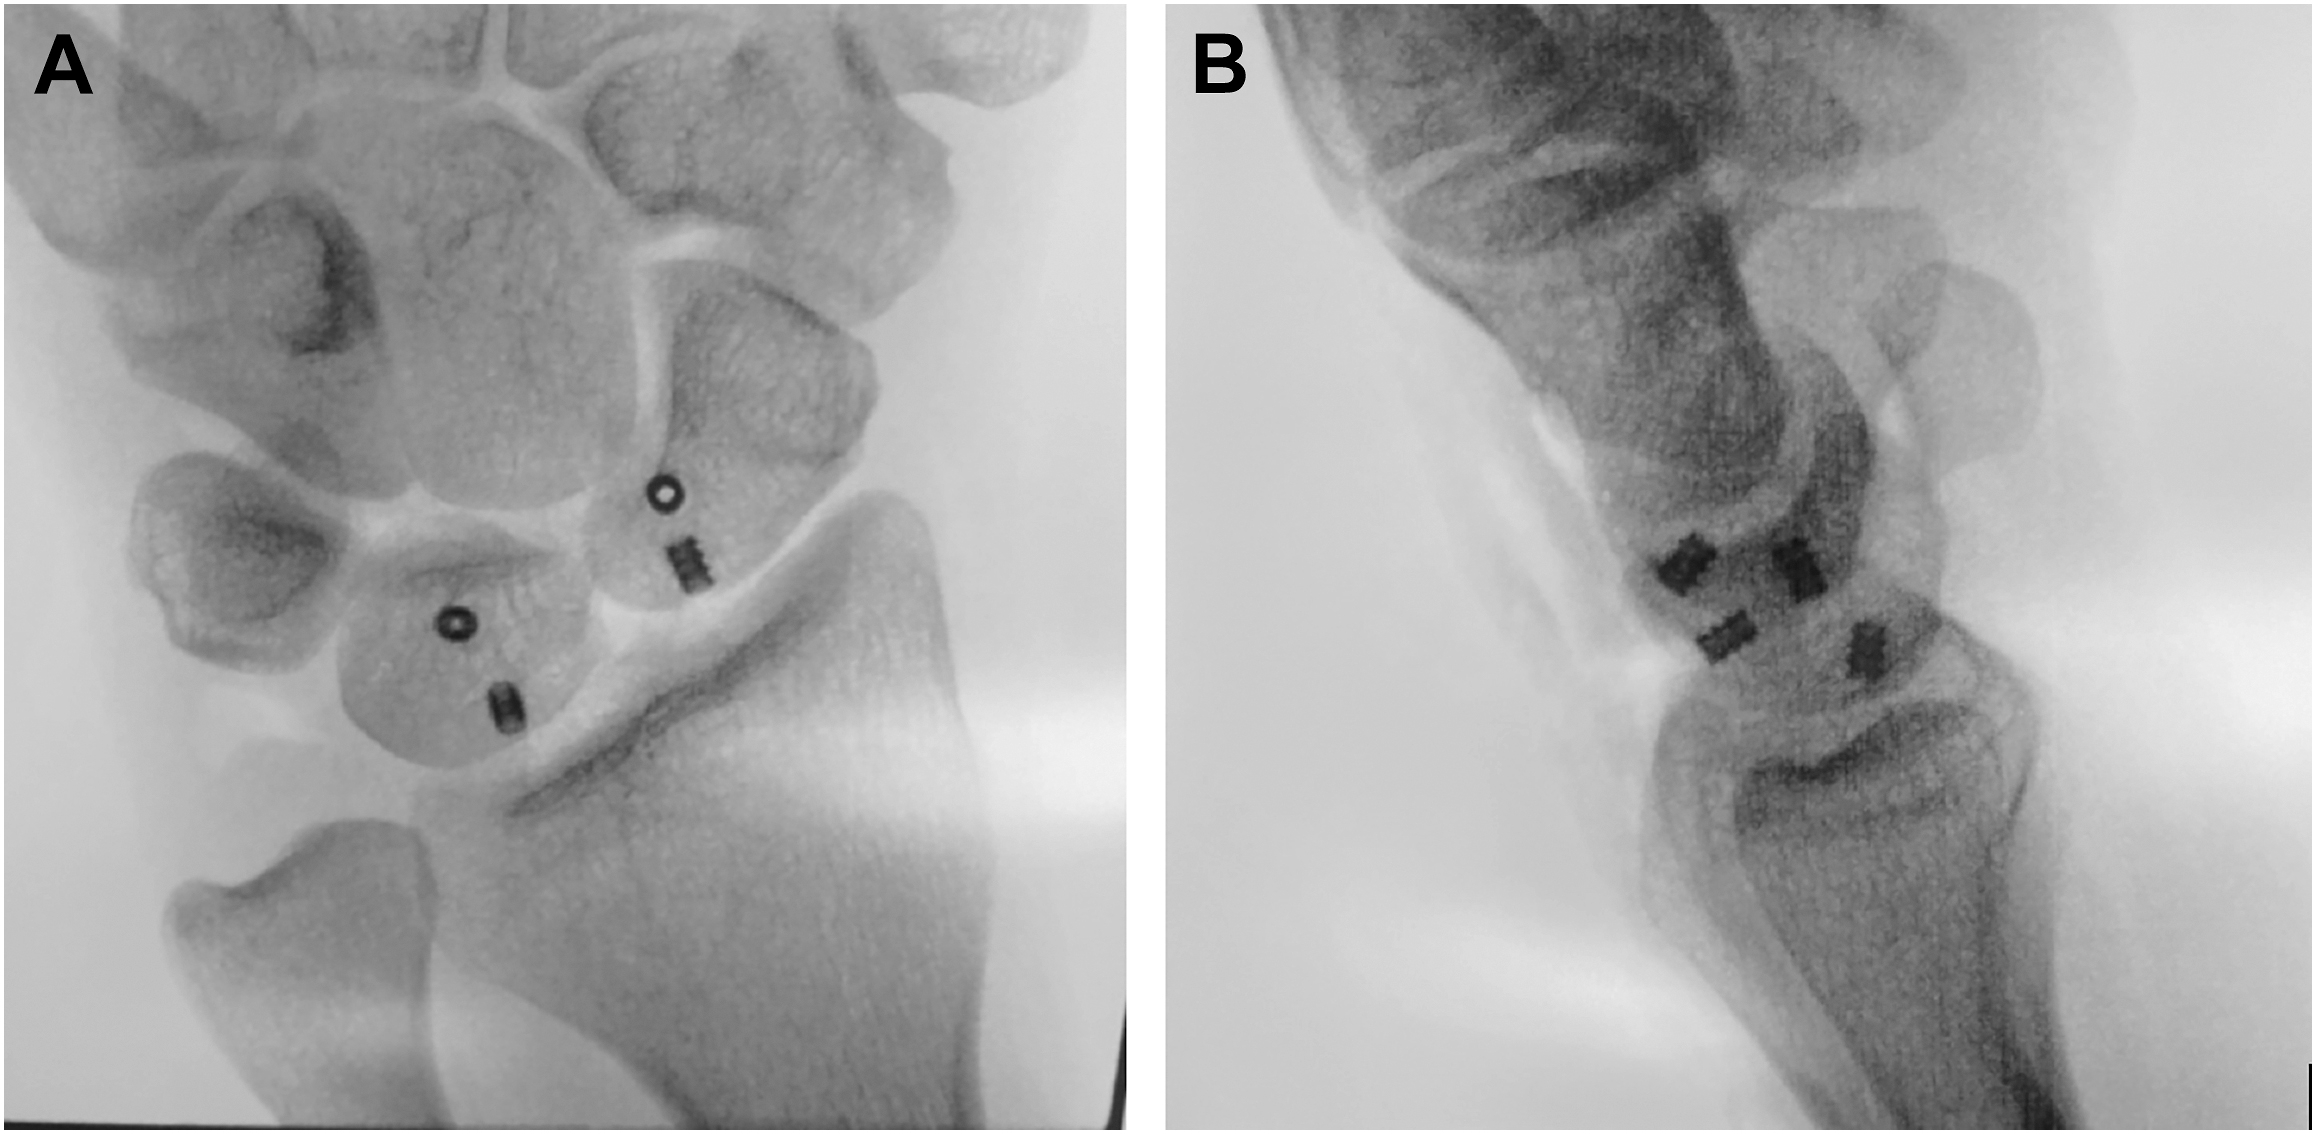

The hook of hamate pull test, described by Wright and colleagues, can be used to further increase the examiner’s suspicion for a hook of hamate fracture. The test is considered positive if pain is encountered with resisted flexion of the ring and small fingers with the wrist placed into ulnar deviation. Suspicion of this injury, however, should be confirmed with standard radiographs and advanced imaging. Posteroanterior (PA), lateral, and oblique views of the wrist may not reveal the fracture. Thus, a carpal tunnel view can be performed if tolerated by the athlete ( Fig. 1 ). The gold standard of diagnosis is the computed tomography, with an accuracy of 97.2% compared with 80.5% for pain radiographs (including all projectional planes). MRI can be used if neurovascular injury or flexor tendon injury is suspected ( Fig. 2 ).

Numerous treatment options for SLIL injuries have been described and are guided by the degree (partial vs complete) and chronicity of injury. Partial tears are initially treated with a period of immobilization, anti-inflammatory medications, and/or cortisone injections. Those who continue to have symptoms may undergo arthroscopic evaluation with possible debridement and thermal shrinkage. For complete tears, open repair or reconstruction may be considered. Though many techniques for this have been described, our preference is internal brace reconstruction with dorsal capsulodesis ( Figs. 3 and 4 A, B ).